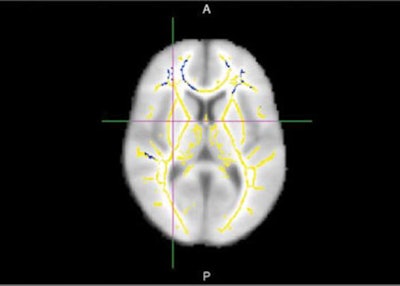

In the current study, the researchers turned to DTI to analyze white-matter integrity in the brain. The tools included fractional anisotropy, which measures the flow of water molecules along white-matter tracts. Higher fractional anisotropy values indicate normal water flow, while lower values indicate disrupted flow and the likelihood of white-matter damage.

In their study, Raji and colleagues reported on 20 patients (average age, 73.4 ± 3.9 years) from the Alzheimer's Disease Neuroimaging Initiative (ADNI). Each subject underwent an MRI scan on a 3-tesla system (Siemens Healthineers or GE Healthcare) with protocols that included T1 volumetric imaging, magnetization-prepared rapid acquisition gradient echo (MP-RAGE), or spoiled gradient-recalled echo (SPGR). From the scans, the researchers obtained values for fractional anisotropy, mean diffusivity, axial diffusivity, and radial diffusivity maps.

Of the 20 patients, half experienced cognitive decline and Alzheimer's disease over various time points up to several years, and half remained cognitively normal. Among the global DTI measures, differences in fractional anisotropy corresponded with progression to Alzheimer's disease, the researchers found. Radial, axial, and mean diffusivity did not show any significant differences, they noted.